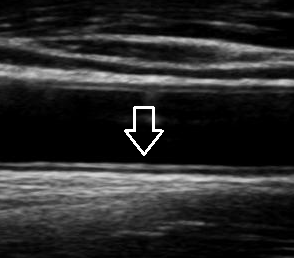

도입부에서 먼저 정리하자면, 경동맥 초음파는 목 양쪽(경동맥)을 초음파로 관찰해 혈관 벽의 두께(내중막두께, IMT), 죽상경화반(플라크), 협착 정도, 혈류 속도와 난류를 평가하는 검사입니다. CT나 MRI처럼 방사선 노출이 없고, 비교적 짧은 시간에 “혈관 상태”를 확인할 수 있어 건강검진에서도 많이 포함됩니다. 다만 이 검사는 ‘병을 확진’하기보다는 동맥경화의 진행 정도와 뇌혈관 사건(뇌경색, 일과성 허혈발작 등) 위험을 정량적으로 추정하고, 치료 방향(약물 강화, 추가 검사, 시술 상담)을 결정하는 데 강점이 있습니다. 즉, 결과 한 장이 ‘지금 당장 큰 문제가 없다’는 확인서가 되기도 하고, 반대로 ‘증상이 없는데도 위험 신호가 있다’는 경고장이 되기도 하므로, 검사 의미를 정확히 이해하고 해석하는 것이 실무적으로 중요합니다.

협착은 혈관이 좁아져 혈류가 제한되는 상태입니다. 초음파에서는 혈관의 내강(통로)을 직접 보기도 하고, 더 중요한 지표로 도플러 혈류 속도(peak systolic velocity 등) 상승, 난류, 좌우 비교를 봅니다.